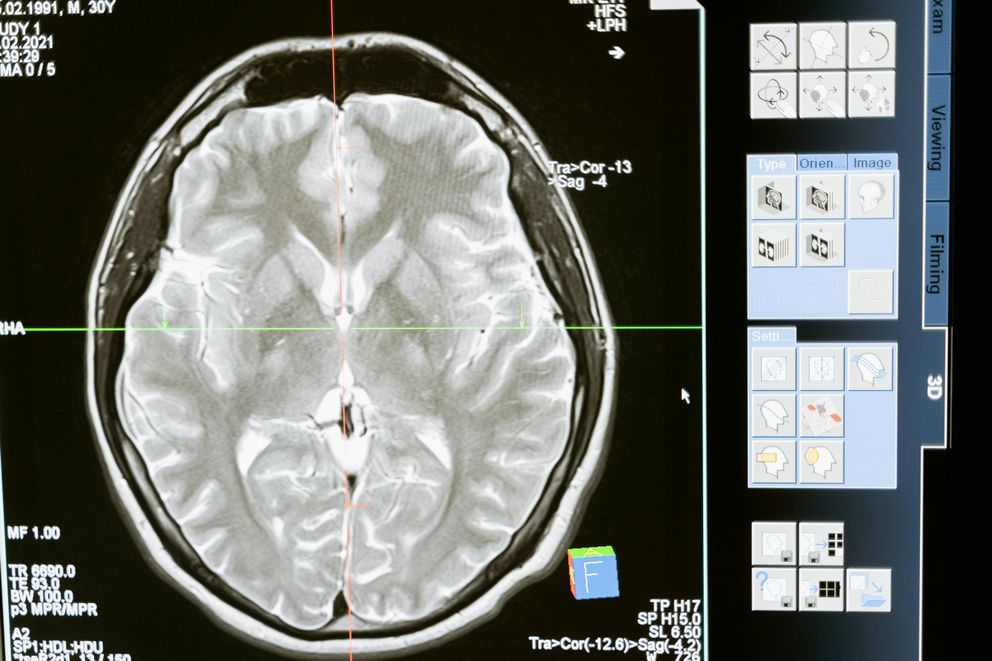

Hello, amazing ladies! If you’ve recently had a stroke or are in the process of recovery, you might be wondering what role your diet can play in your journey back to health. The great news is that your food choices can have a massive impact on your recovery and long-term well-being.

Let’s explore the best diets for women after a stroke in 2024—diets that are not just healthy but also delicious and easy to follow.